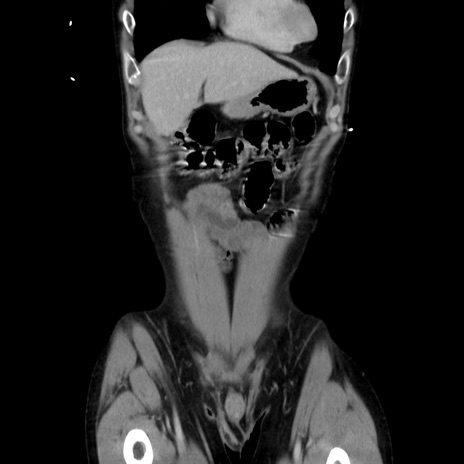

症例37(冠状断像)

【症例】40歳代 男性

【主訴】腹痛

【現病歴】4時間ほど前に電車に乗車中に臍部上より腹痛出現。徐々に増悪し起立困難となり、救急外来受診。生ものは数日食べていない。今朝お雑煮を食べた。

【身体所見】BT 36.8℃、BP 117/84mmHg、HR 91/min、SpO2 97%、苦悶様、腹部:臍上部広範囲圧痛あり、反跳痛±

【データ】WBC 8100、CRP 0.03